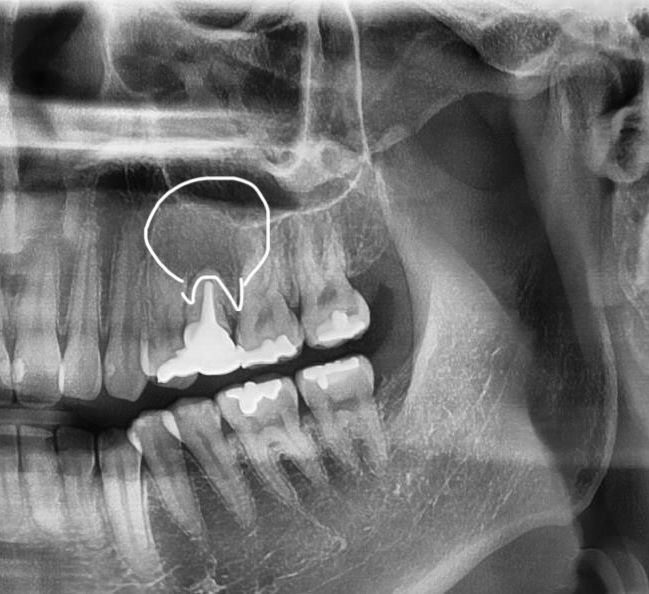

사진 찍고 진료받아보니 뿌리 쪽 잇몸 안에 큰 물혹 염증 같은 게 가득 차 있다고 크기도 많이 크고 상태가 만히 안 좋다 하셔서

많이 심각한 거라고도 얘기를 하셔서 양성종양 같은 거라고도 하시던데

뿌리의 병수의 크기로 보면 최근에 생긴 것이 아니라 오랜 기간 동안 진행된 것으로 보입니다. 뿌리 끝에 병소가 너무 크다면 신경치료 등으로 해결이 되지 않을 수도 있기 때문에 큰 병원에서의 치료가 필요할 수 있습니다. 자세한 확인을 위해서 치과에서 진료를 받아보세요.

안녕하세요 치과의사 김철진입니다. 치아때문에 생긴 염증이라면 치근단 절제술을 해볼수 잇지만 낭종이라면 수술적으로 제거를 하셔야될것같습니다.

뿌리끝 염증에서 비롯되는 물혹의 가능성이 있어보입니다. 현재로선 완전히 cyst화된 건 아니고 granular tissue 의 상태로 보여집니다.

발치도 염두는 해두셔야 하고 치근단절제술 등이 시도될 수는 있을 것 같습니다.